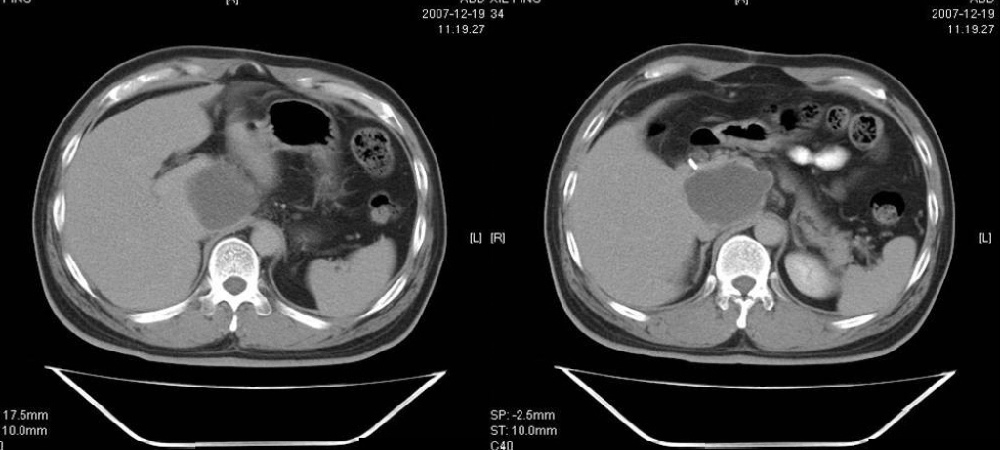

考虑十二指肠憩室。从影像上看,病变位于下腔静脉前胰头后方十二指肠内侧,肝尾叶受压,说明病变来源于后腹膜;胰胆管成像胰管和胆道未见扩张,总胆管中段受压未显示,上下段正常,所以不考虑来源与于肝尾叶和总胆管的囊肿。考虑为十二指肠憩室或小网膜囊肿。

楼上高手,本例的确是一例十二指肠憩室.

考虑十二指肠憩室。从影像上看,病变位于下腔静脉前胰头后方十二指肠内侧,肝尾叶受压,说明病变来源于后腹膜;胰胆管成像胰管和胆道未见扩张,总胆管中段受压未显示,上下段正常,所以不考虑来源与于肝尾叶和总胆管的囊肿。考虑为十二指肠憩室或小网膜囊肿.分析的好。